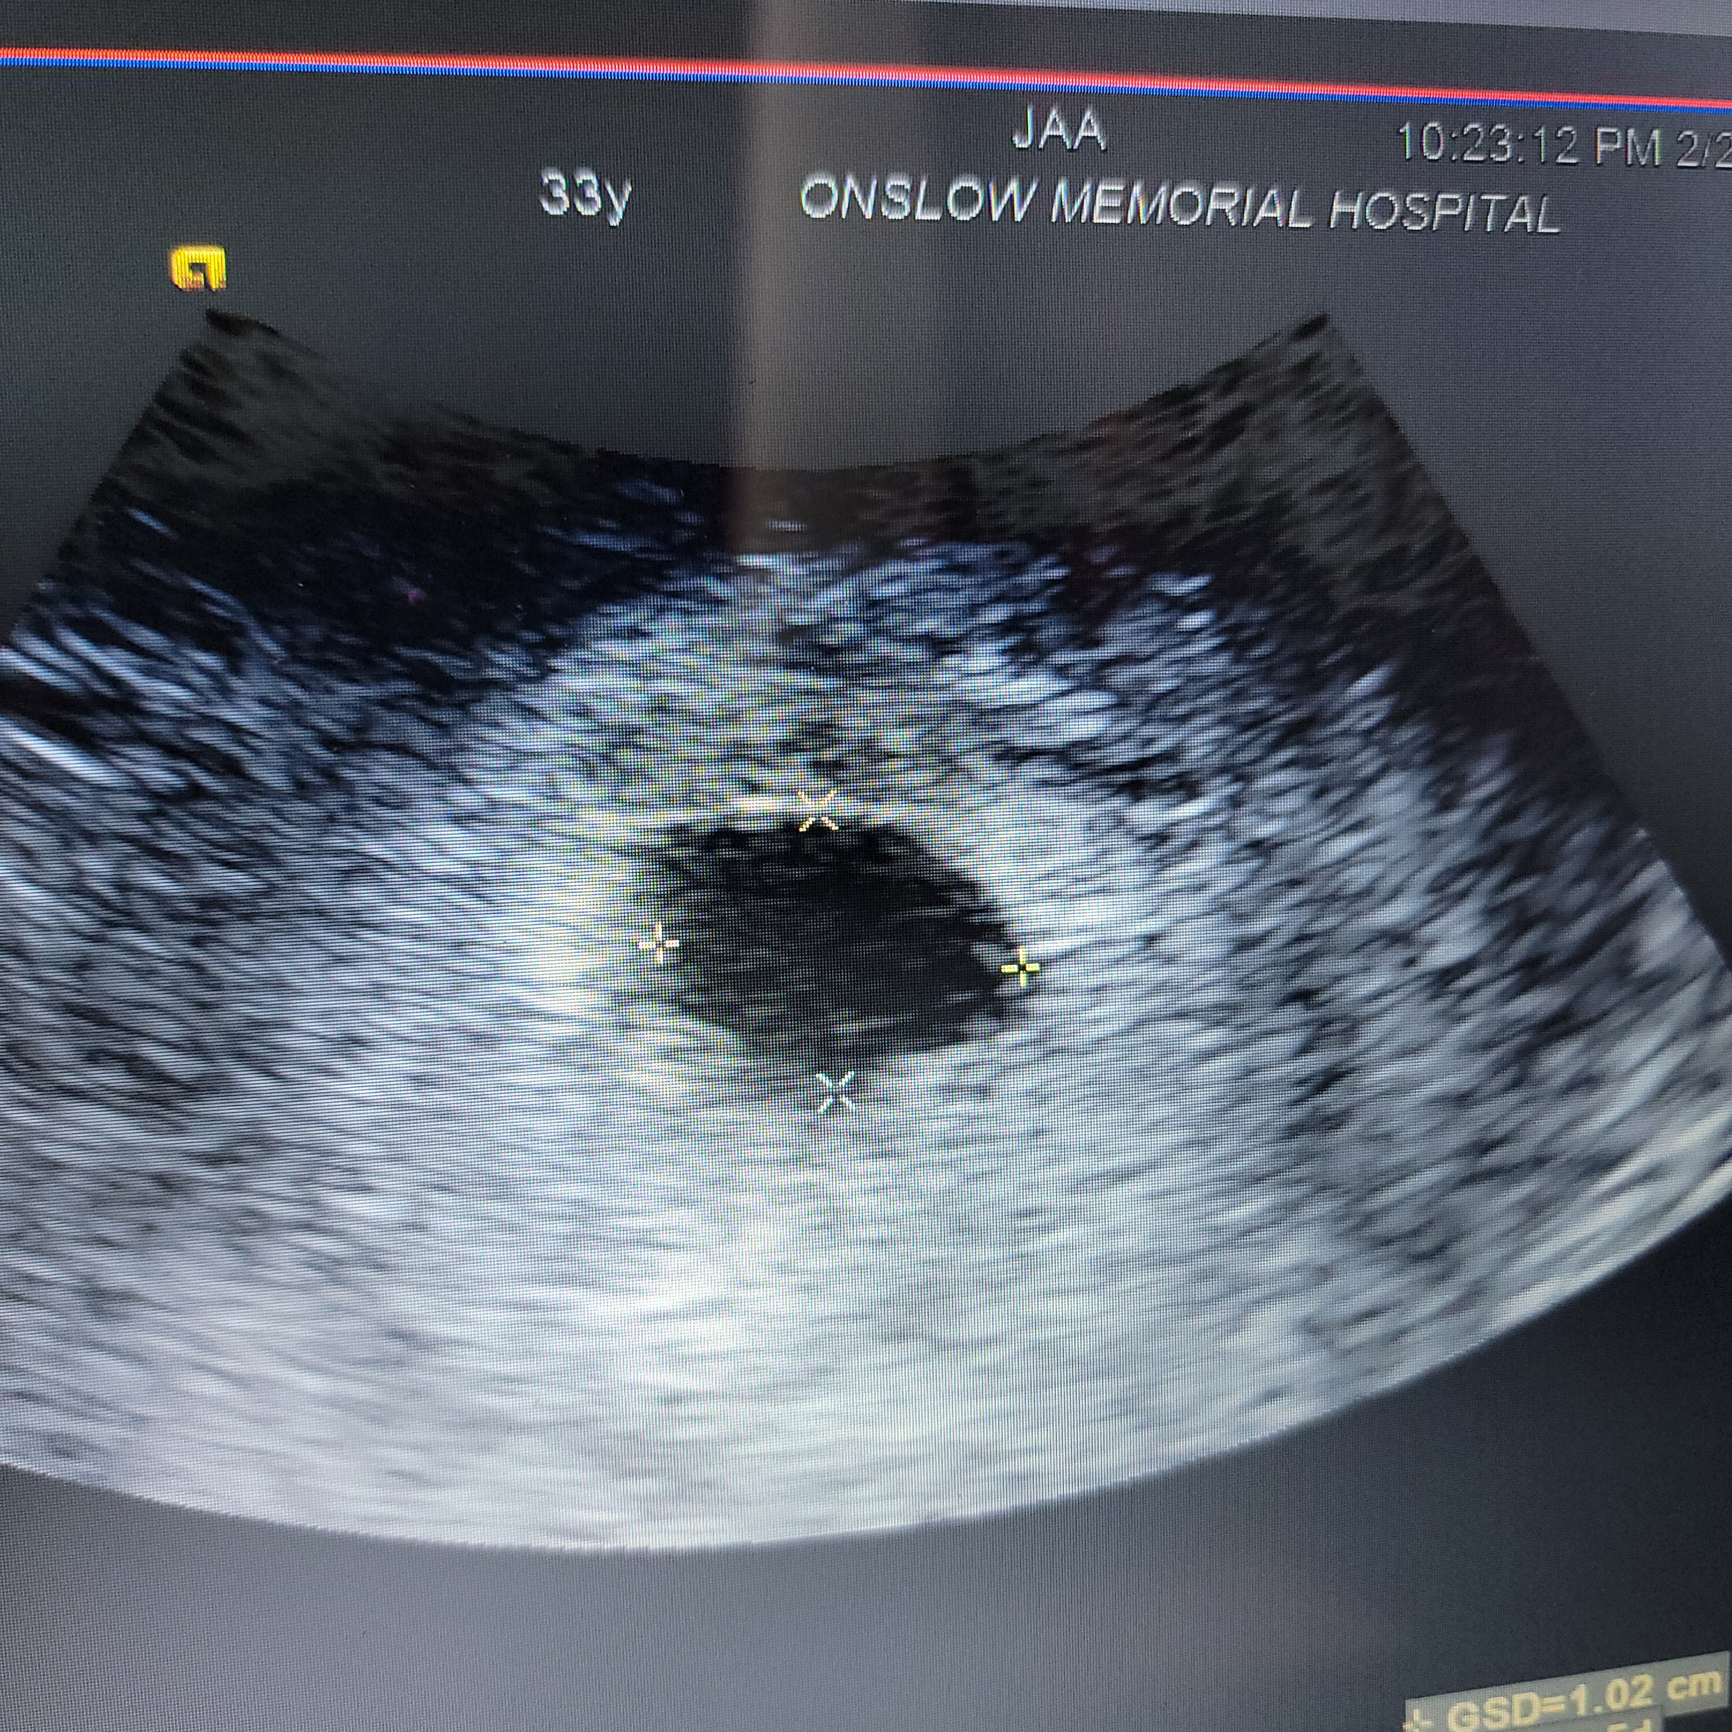

I went to the ER last night for pelvic pain at 5 weeks 5 days. Hcg was 18,000 but only a gestational sac was seen and a subchorionic hemorrhage. I'm so scared it's another blighted ovum 😭 This would make our 10th loss and I refuse to do this anymore. 😭😭😭

Re: Possibly 10th Loss